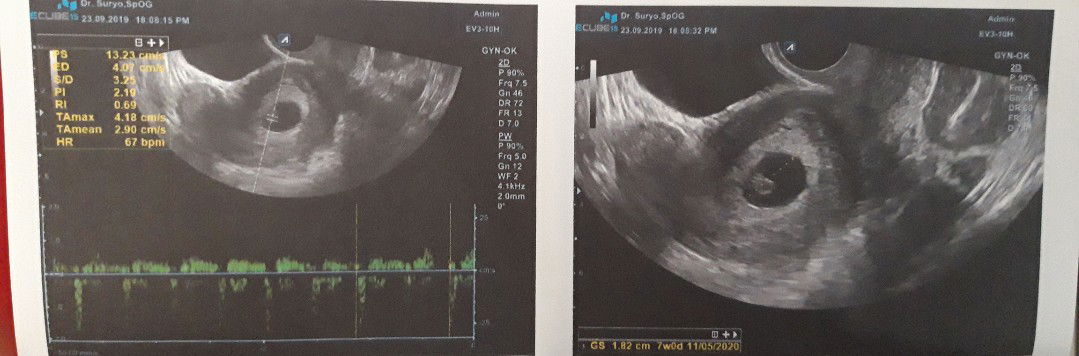

Alhamdulillah bunda, berkat saran dari bunda" buat cari second opinion dri dr. Lain hasilnya memuaskan. Dan bersyukur banget gak di minum obat peluruh yg di suruh minum sama dr. Yg 1 nya. Yg katanya anaknya gak berkmbang usia hnya 5W harus di kuret/mnum obat pluruh, namun 2 hari kemudian di cba cari dr. yg lebih dari itu Alhamdulillah dr.nya bilang untung gak ibu keluarkan dan di minum obatnya, usia nya 7W baby nya sehat sama detak jantungnya pun udah kedengran ??.

Bun, mau nanya ada gak yg stlah usg dr. Nya diagnosa janin tidak berkembang namun dg keyakinan hati tetap diprthankan dan hasilnya diluar pendpat dr. Nya bunda? Mohon jwabannya y bun ☹

Bunda mau nanya, sya kan udah hitungan 8w2d dg hit. Aplikasi, namun tdi pagi saya keluar flek tetesn aja. Nah saya bawa ke dokter usg dan tes lab. Positif, namun di i Usg usianya 5w dr. Nya bilang gak berkembang dan msti di kuret. Bagaimana pendapat bunda? Bantu yaaa